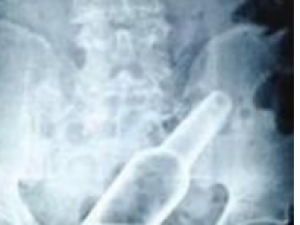

小编导读:通过腹部CT检查,在距离男孩肛门口7厘米的地方发现了一个拇指长、一圆硬币粗的完整玻璃瓶。25日晚上8点半,只听一阵急切的呼喊:一对面色焦急的父母带着一个表情尴尬的男孩急匆匆跑了进来。男孩红着脸..